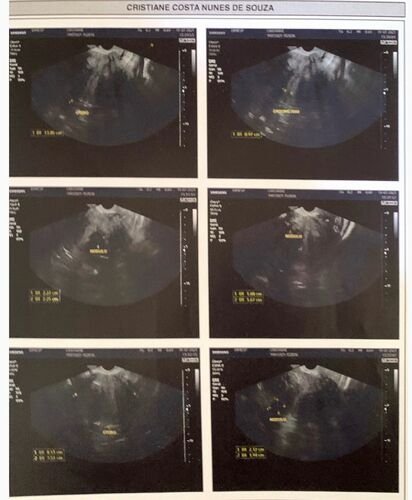

Meu nome é Cristiane Costa, tenho 45 anos e sou moradora de Campo Grande - Rio de Janeiro. Fui diagnosticada com mioma uterino em 2018 até o momento eu estava fazendo o tratamento do mesmo com o uso contínuo de anticoncepcional, que era usado para o controle de sangramento e cólicas menstruais. Infelizmente como mostra na ultrassonografia eu possuo miomas intramural, meu útero está 4 vezes maior que o normal, estou tento hemorragia frequentemente, o que acabou provocando uma anemia e minha taxa de hemoglobina está 8,00 g/dL muito baixo e preocupante, pois caso não seja tratada a mesma pode se tornar uma leucemia.Eu já estou na fila do SUS para realizar a cirurgia, porém sabemos que isso pode levar anos e anos para que eu seja chamada para finalmente realizar a cirurgia de retirada dos miomas, no cenário atual em que me encontro bem fraca devido à anemia eu não posso esperar anos para a realização da cirurgia, com isso venho através dessa vaquinha pedir a ajuda de vocês para que eu consiga realizar esta cirurgia o mais rápido possível pelo hospital particular, eu fiz uma pesquisa e o lugar onde essa cirurgia é mais em conta é na Casa de saúde N.S Aparecida, que fica localizada em Paracambi, porém antes de realizar a cirurgia eu precisarei tratar a anemia, o que irá gerar mais custos, pois eu terei que fazer um tratamento com um médico especialista em hematologia. Fiz uma estimativa dos custos e aproximadamente precisarei do valor de R$: 10.000 reais.